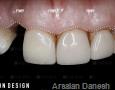

9 Months

12 Months

15 Months